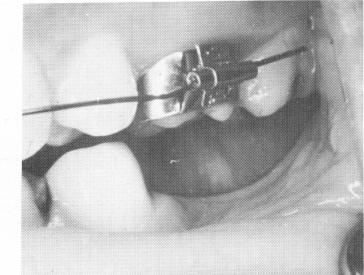

Fig. 15-90. A lower edentulous posterior area with an upper arch wire and molar band with buccal tube is seen.

3 Lower edentulous area with upper arch wire,molar band with buccal tube

for a fixed partial denture. A buccal tube was processed to the buccal surface of the crown covering the implant (Fig. 15-92).

The intermaxillary rubber band extended from the maxillary hook attached to the labial arch wire back to the buccal tube on the mandibular crown covering the implant (Fig. 15-93) . It was worn 24

hours a day, thus speeding the reduction of the over-bite and overjet.